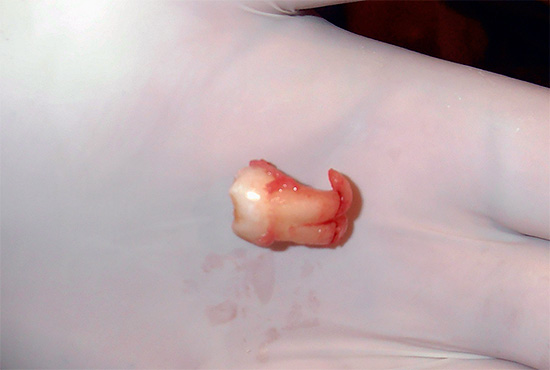

Questo vale, prima di tutto, per le radici del dente, che possono piegarsi in qualche modo nella mascella, solo per dare alla parte della corona l'opportunità di girare in modo tale da venire ancora in superficie da sotto la gengiva e stare in piedi nella dentatura. Il risultato di tutte queste "prove sulla via della luce" è la flessione delle radici del dente del giudizio, unica per ogni persona, e talvolta la sua posizione assolutamente incredibile nella dentatura (se, ovviamente, taglia la gomma).

- radici fortemente curve (a volte anche ad angolo retto - vedi l'esempio nella foto);